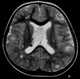

Subependymal giant cell astrocytoma

Subependymal giant cell astrocytoma (SEGA, SGCA, or SGCT) is a low-grade astrocytic brain tumor (astrocytoma) that arises within the ventricles of the brain. It is most commonly associated with tuberous sclerosis complex (TSC). [Source: Wikipedia ]